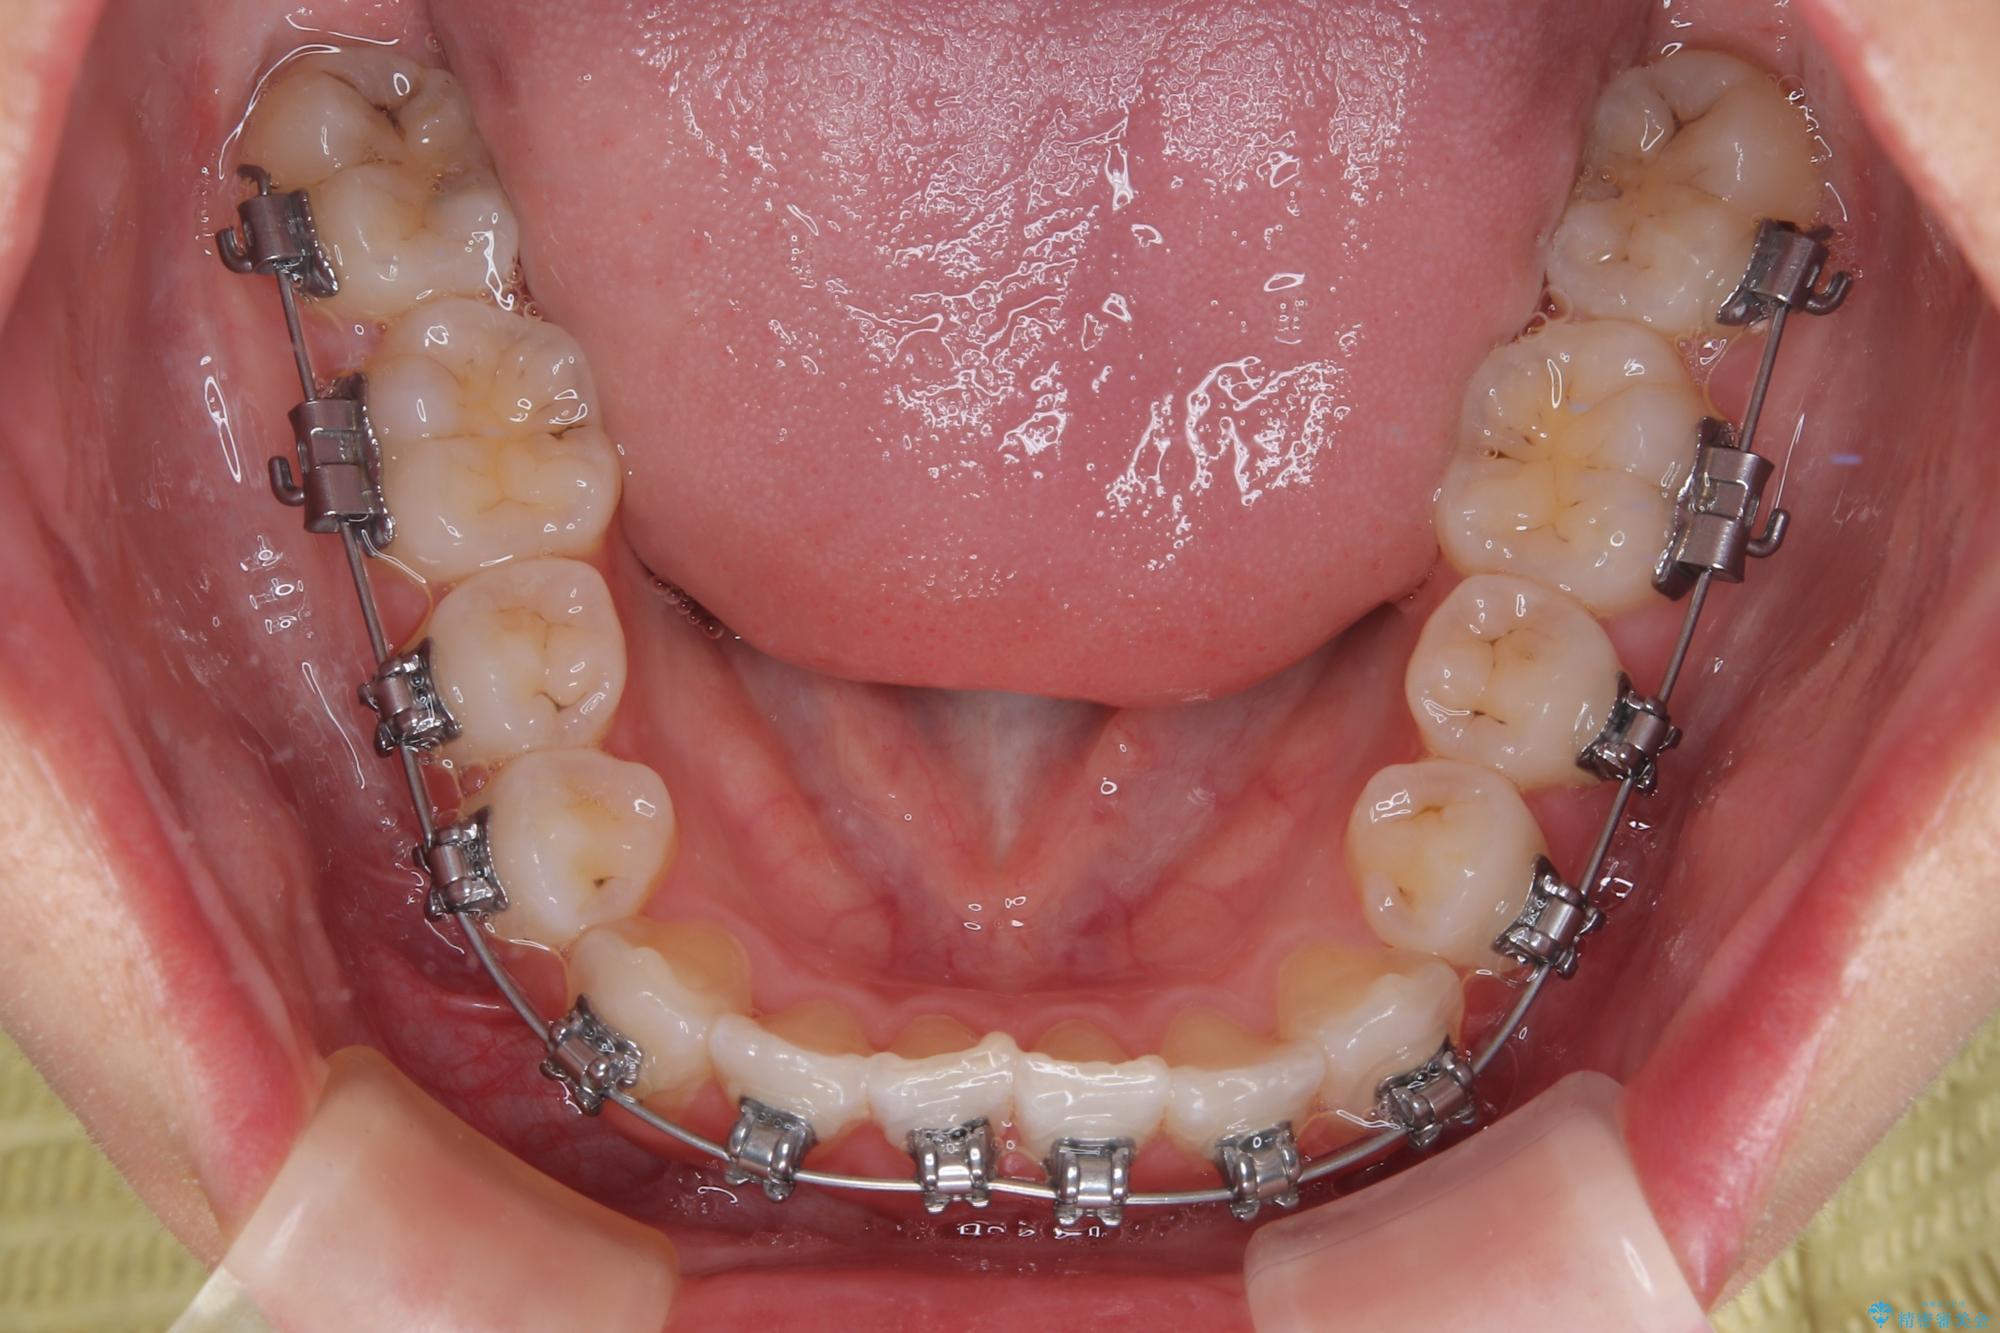

- 矯正装置

- メタルブラケット

- 上顎前歯のクロスバイトを気にして来院された患者様です。

ワイヤー矯正でもマウスピース矯正でも対応可能でしたが、マウスピースによる自己管理に一切の自信がないとのことで、ワイヤー装置にて矯正治療を行うこととしました。

装置の外見を気にしていましたが、短期間で治療を終えることができるだろうと伝えると、安価であるメタルブラケットを選択されました。

想定通り、1年強で綺麗に仕上げることができました。